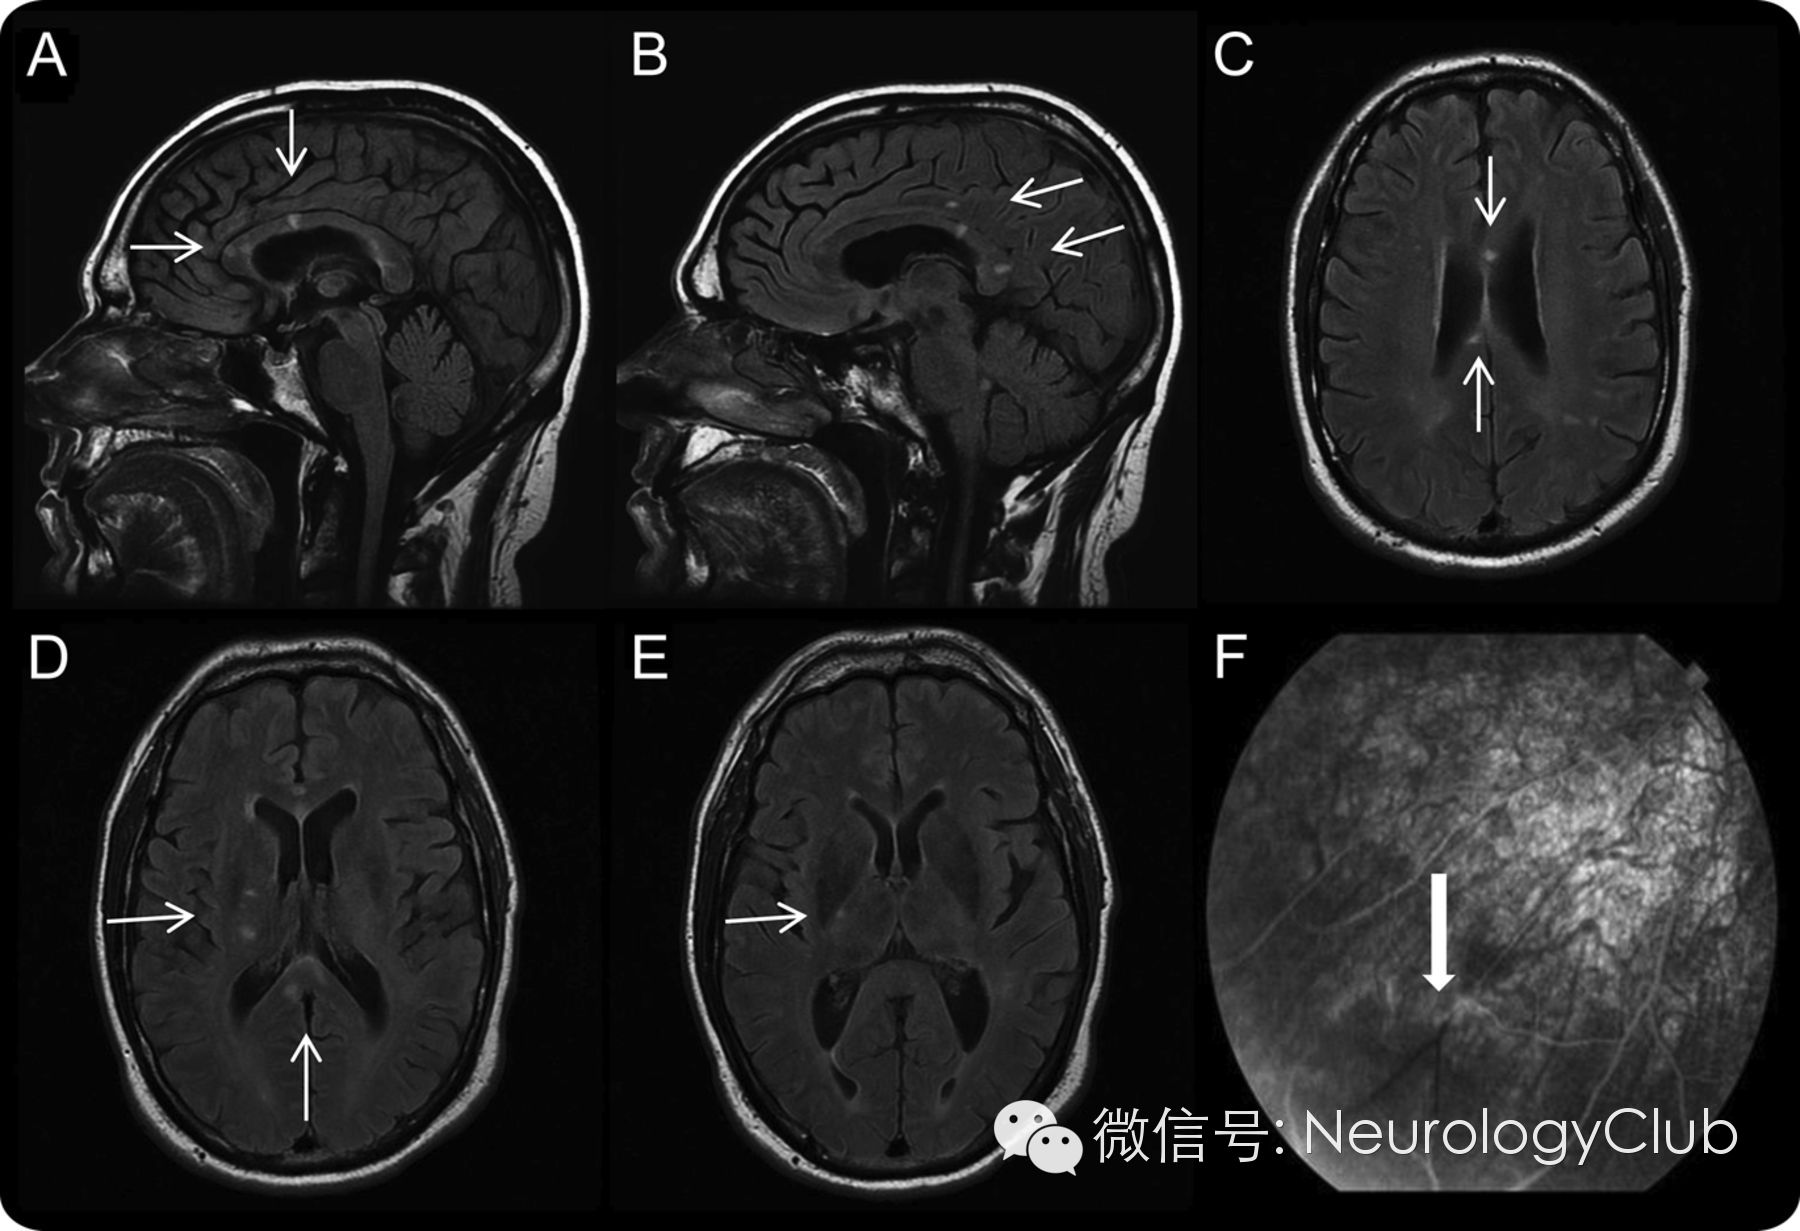

头颅MRI(黑水像)及眼底荧光血管造影如下:

(A-C:雪球样圆形病灶,直径<10mm,主要位于胼胝体中央;D-E:也可见脑室旁和皮质下病灶;F:视网膜动脉分支闭塞)

位于胼胝体中央的雪球样病灶是本病特征性的MRI改变,提示毛细血管前微动脉闭塞。因主要累及小血管,故多数病例血管造影正常。临床上如遇到难以解释的听力缺失以及胼胝体雪球样病变时,行眼底荧光血管造影有助于诊断。